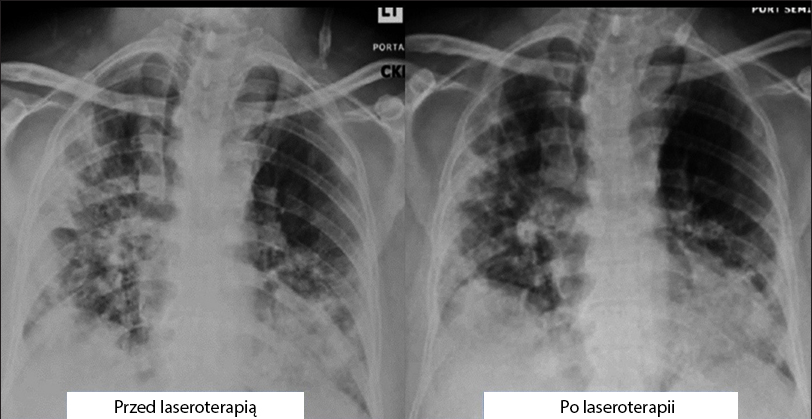

Skala radiologicznej oceny obrzęku płuc (Radiographic Assessment of Lung Edema, RALE) [28,29] ocenia obrzęk płuc na podstawie RTG klatki piersiowej u pacjentów z ARDS. W celu ilościowego określenia zakresu zakażenia obliczono skalę jego ciężkości [29]. Każdemu płucu przypisano wynik od 0 do 4 w zależności od procentu zagęszczenia tkanki płucnej wskutek nacieku lub zacienienia typu matowego szkła, gdzie 0 oznacza brak zajęcia płuc, 1 oznacza 75%. Wyniki dla każdego płuca zostały zsumowane, aby otrzymać ostateczną ocenę ciężkości [29]. Wynik RALE wyniósł 8 (> 75% zajęcia obu płuc) i poprawił się do 5 po zakończeniu leczenia (rys. 3).

rysunek 3

Radiograficzna ocena obrzęku płuc (RALE) metodą RTG klatki piersiowej wykazała redukcję zagęszczenia tkanki płucnej i zacienienia typu matowego szkła po PBMT. Ocena radiologiczna płuc zależy od stopnia zajęcia na podstawie zagęszczenia lub zacienienia typu matowego szkła w każdym płucu. Całkowity wynik to suma punktów uzyskanych dla obu płuc. Klasyfikacja punktowa: 0 – brak zajęcia płuc; 1 – zajęcie płuc 75%. Wynik RALE przed laseroterapią (27.04.2020) = 8. Laseroterapię rozpoczęto 29.04.2020 r. Wynik RALE po laseroterapii (05-03-2020) = 5.